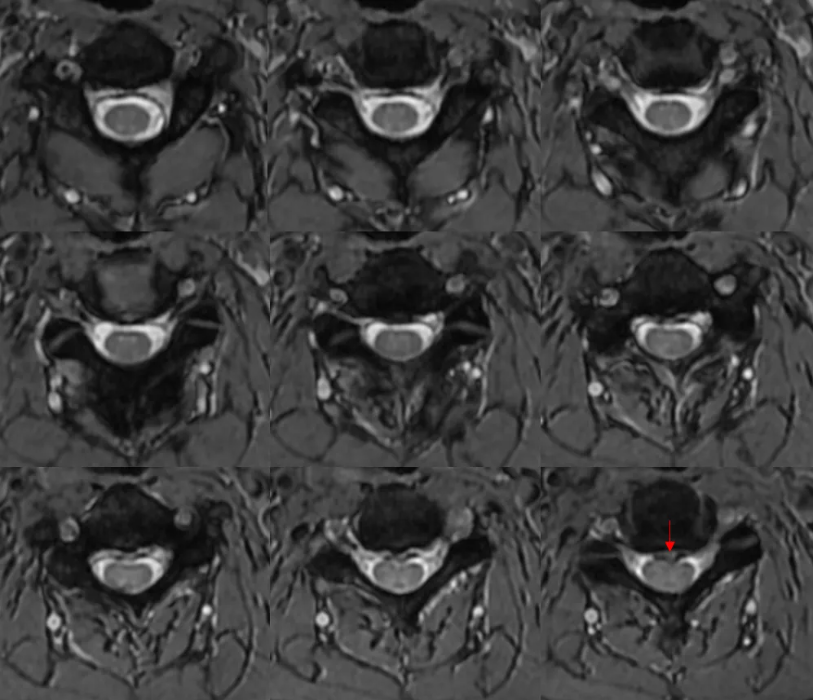

很简单。 椎间盘突出。 想看清椎间盘突出,最好用的序列莫过于横断面梯度回波序列T2*WI MERGE(multiecho recalled gradient echo,多回波的梯度回波序列)。与常规T2WI FSE序列相比,其优点在于脑脊液流空伪影很少。所以,脑脊液呈显著高信号,突出的椎间盘呈低信号,二者之间对比差异很大,图像效果杠杠滴。

小编以后也要注意脊柱大保健了(写到此处,小编无意识地活动了一下脖子)。 横断面T2*WI 梯度回波序列还有一个特点,脊髓的小蝴蝶显示比较好。 感觉这个患者小蝴蝶显示很一般啊。 这个垃圾机器。曾经有个教授的课件,小蝴蝶可漂亮了。。。 再翻一遍图像,好像脊髓怪怪的。